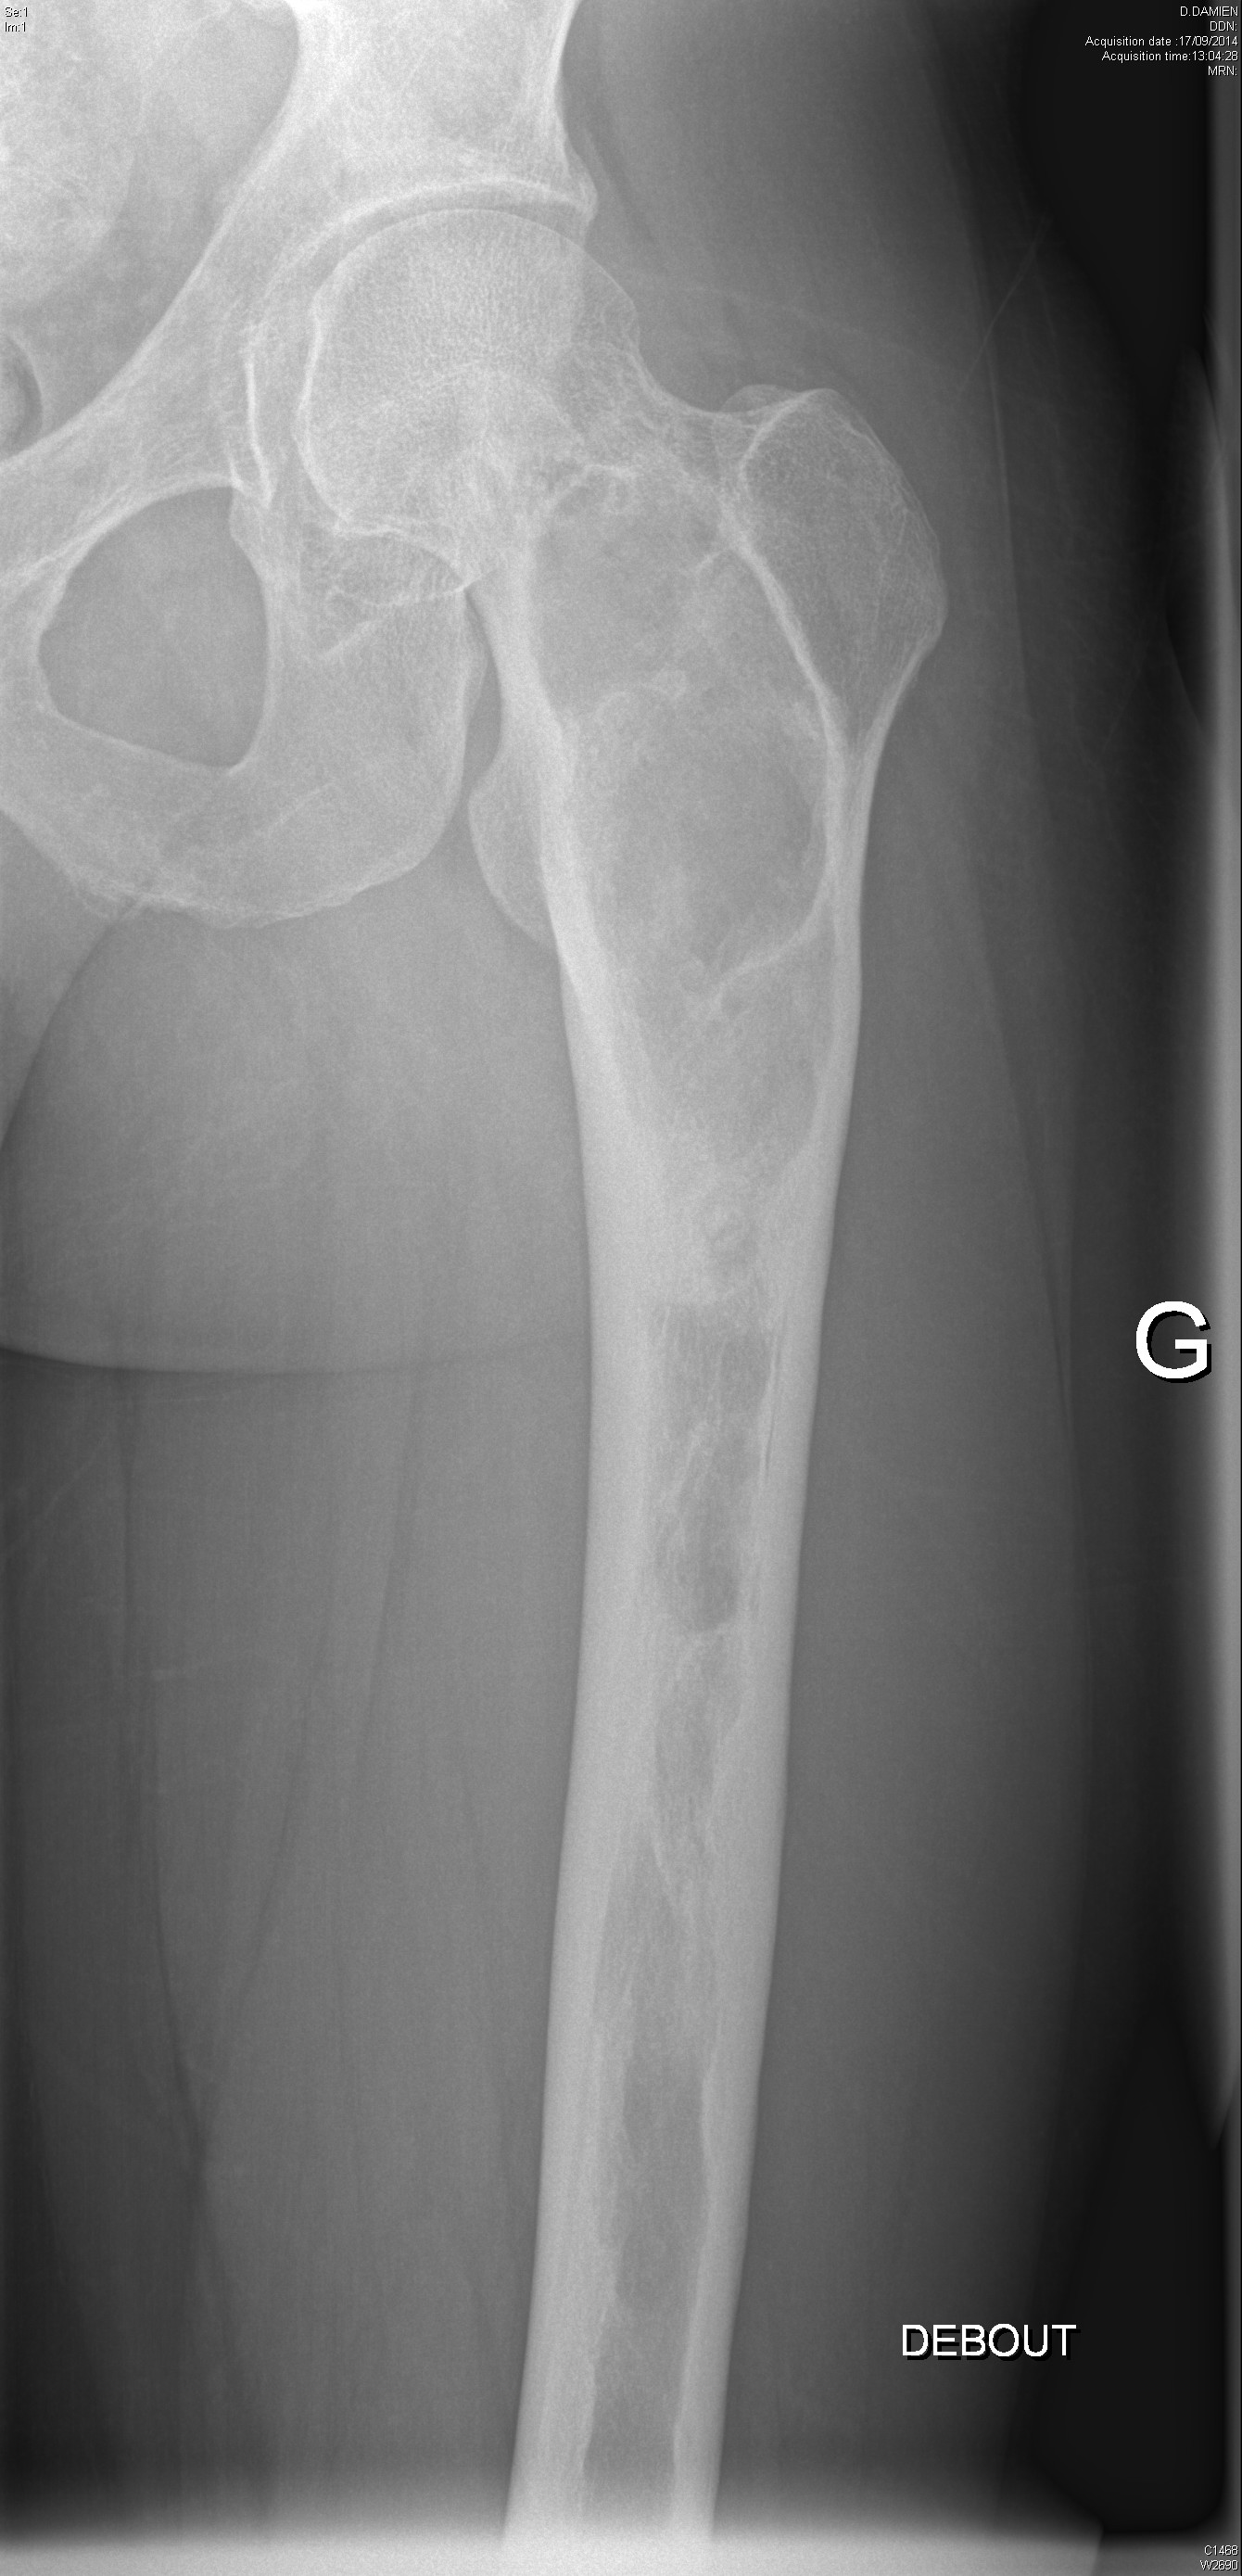

Dysplasie fibreuse du fémur gauche dans un contexte de dysplasie fibreuse polyostotique

Fracture fémorale atypique sous biphosphonates